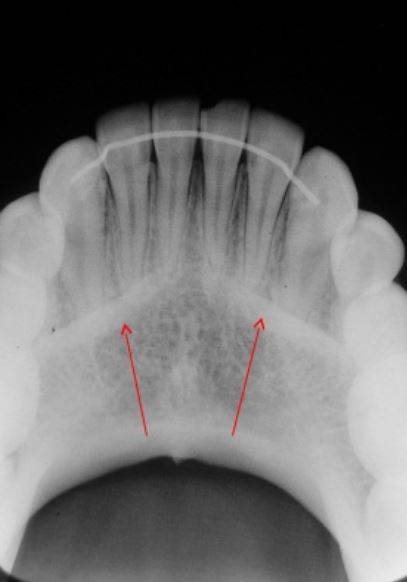

QUE ESTRUCTURA ANATOMICA SE ENCUENTRA SENALADA EN LA IMAGEN

Escoge una o varias respuestas